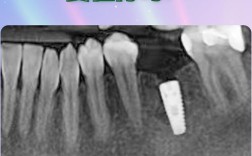

⚠️ 临床警示信号:CBCT三维影像显示可用骨高度<8mm、宽度<5mm,或骨密度T值≤-2.5SD(骨质疏松)时,必须优先考虑增量手术。